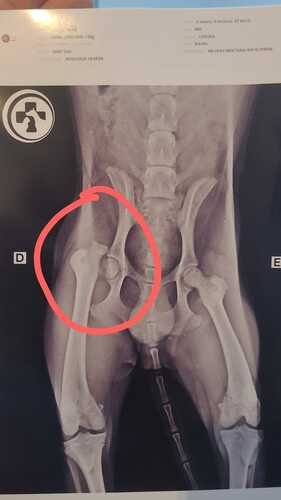

(05/06) Oi, eu sou o Max eu fui atropelado e tenho duas fraturas na minha perninha. Meu AUmigo me resgatou, me levou no médico e está cuidando de mim, mas as depesas são muito caras e ele não consegue pagar sozinho.

A cirurgia e os gastos inclusos (remedios, internação, exames) giram em torno de R$ 7.000,00 reais. Me ajude, por favor, sozinho meu AUmigo não consegue dar conta. Eu preciso MUITO da ajuda de vocês, muito AUbrigado por qualquer ajuda. Lambeijos do seu amigo MaX!